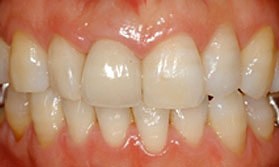

After

| 主訴 | 歯冠破折 |

| 年齢・性別 | 8歳 男子 |

| 治療期間・回数 | 複数回 |

| 治療方法 | 見えていた歯髄の表層をとり(断髄し)、歯髄の傷が治りやすい薬で傷口を保護しました。その後、折れた破折片を、修復材にてもとの歯に接着しました。 |

| 費用 | 保険適用 |

| デメリット・注意点 | 定期的なレントゲンでのチェックが必要 |